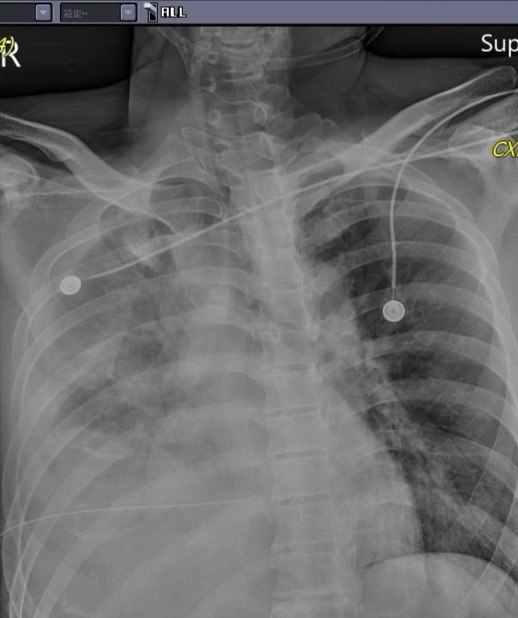

這位受傷的林姓男子,本來是為了上前幫助受傷女童,沒想到卻意外遭砍傷,馮啟彥醫師日前也透露了傷況,「胸、腹、背部都被利刃刺出很大又很深的傷口,本來以為只有氣血胸,但是置放胸管後,仍有持續性出血現象」,甚至得由胸腔外科及一般外科醫師聯手一起介入手術;而在晚間手術後,更發現肺臟破裂引發氣血胸,「而且因為利刃穿刺很深,橫膈膜及肝臟都有破裂及大量出血現象!」所幸在手術後,男子病情已經比較穩定,雖然仍插著呼吸器,但已經能夠清醒的與大家致意。